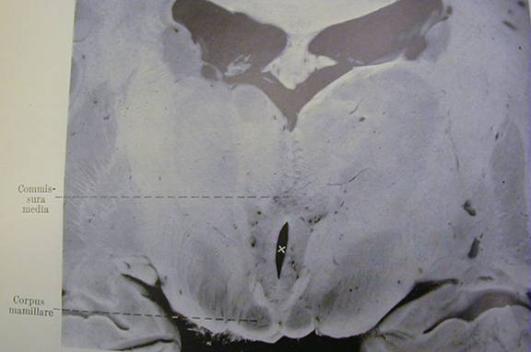

capillaries. Figure 8 (from Kant's 1933 article) is a

photograph showing the hemorrhagic damage in the

inferior colliculi and tissue surrounding the aqueduct.

Figure 8 - From Kant (1933). Corpora quadrigeminae posterior, another name for

|